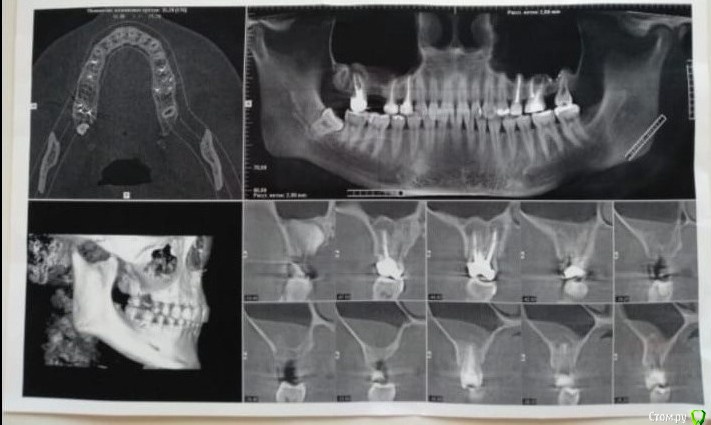

Добрый день! Обращаюсь к Вам за помощью, так как мнения врачей разделились, а я уже и не знаю, что думать. Над 5-м зубом возник свищ, сейчас он есть уже на протяжении 3-х месяцев, началось с того, что летом был гайморит и было сильное давление на область зубов (там, где установлен мост), в итоге, пила антибиотики и в целом состояние улучшилось. При этом не проходило ощущение давления в пазухе, стоматолог предложила проставить в десну линкомицин, дабы воспаление уменьшилось, после проставленных уколов, образовался свищ, тяжесть в пазухе так же присутствует. Стоматолог-терапевт говорит подождать, может, пройдет. Хирург говорит удалять 5 и 7, ставить имплантаты. Прилагаю снимок и прошу вашей помощи. Что же делать в данной ситуации? Есть ли шанс на то, что зуб можно сохранить? Может, стоит сделать резекцию верхушки?

Один снимок до мостовидного протеза (2019 год), второй сентябрь 2020.

Зуб 17, по моему мнению, придётся удалить; про 15 недостаточно информации. Неплохо бы свежую комп. томографию посмотреть (хотя бы от 09.2020), а не снимки скришотов с монитора. Постарайтесь выложить. Инструкция, как это сделать в самом начале пациентского раздела.